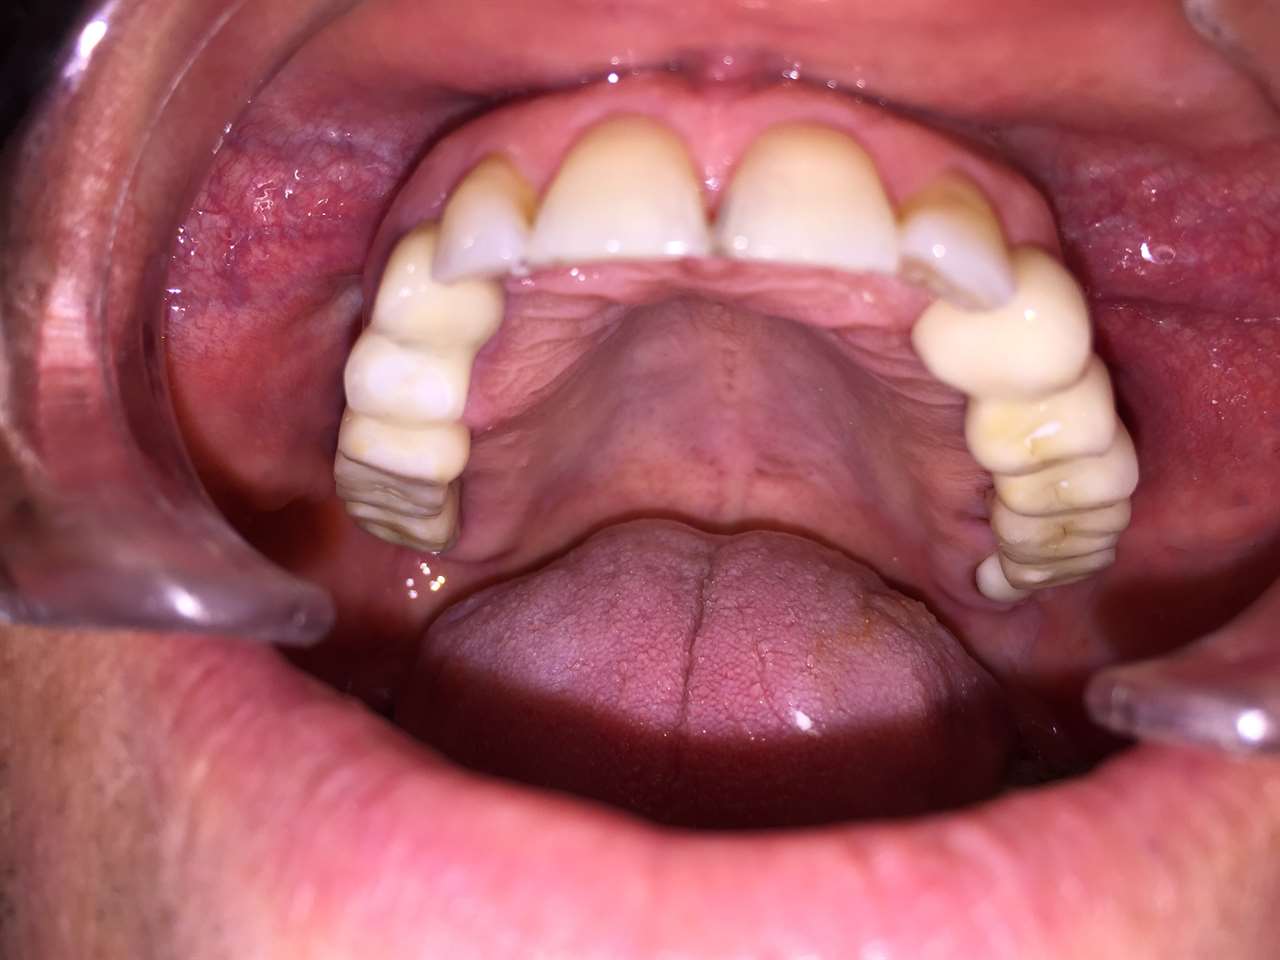

Elhanyagolt fogsor cseréje 2 nap alatt

2 nap alatt varázsoltuk ezt a szép esztétikus alsó, felső körhídat implantátumokkal megtámasztva a korábban elhanyagolt szájba. Az 1. nap 26 fogat távolítottunk el, mert annyira rossz állapotban voltak, és rögtön azonnal terhelhető IHDE svájci implantátumokat raktunk be, fentre 8, lentre 6 darabot. A sebeket összevarrtuk és intraorális szkennerrel digitális lenyomatot vettünk. 2 nap múlva pedig beragasztottuk a kész PMMA műanyag körhidakat. Dr. Kelemen Péter és a Symbion Fogtechnika munkája.